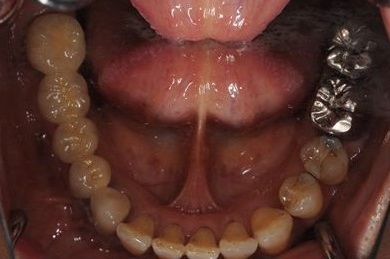

インプラントの症例写真 IMPLANT

抜歯即日スピードインプラント治療

| 性別/年齢 | 女性 / 44歳 | ||||||||||||||||||||||||||||||||

| 主訴 | 上のさし歯がグラグラする。インプラントにした方が良いのか、相談したい。 | ||||||||||||||||||||||||||||||||

| 治療方針 | 抜歯と同時にインプラントを埋入し、治療期間を短縮する。 | ||||||||||||||||||||||||||||||||

| 治療内容 | インプラント2本(抜歯即日スピードインプラント)、メタルボンドセラミック2本 | ||||||||||||||||||||||||||||||||

| 総治療費 | 458,588円 | ||||||||||||||||||||||||||||||||

| 治療期間 | 6ヶ月 |